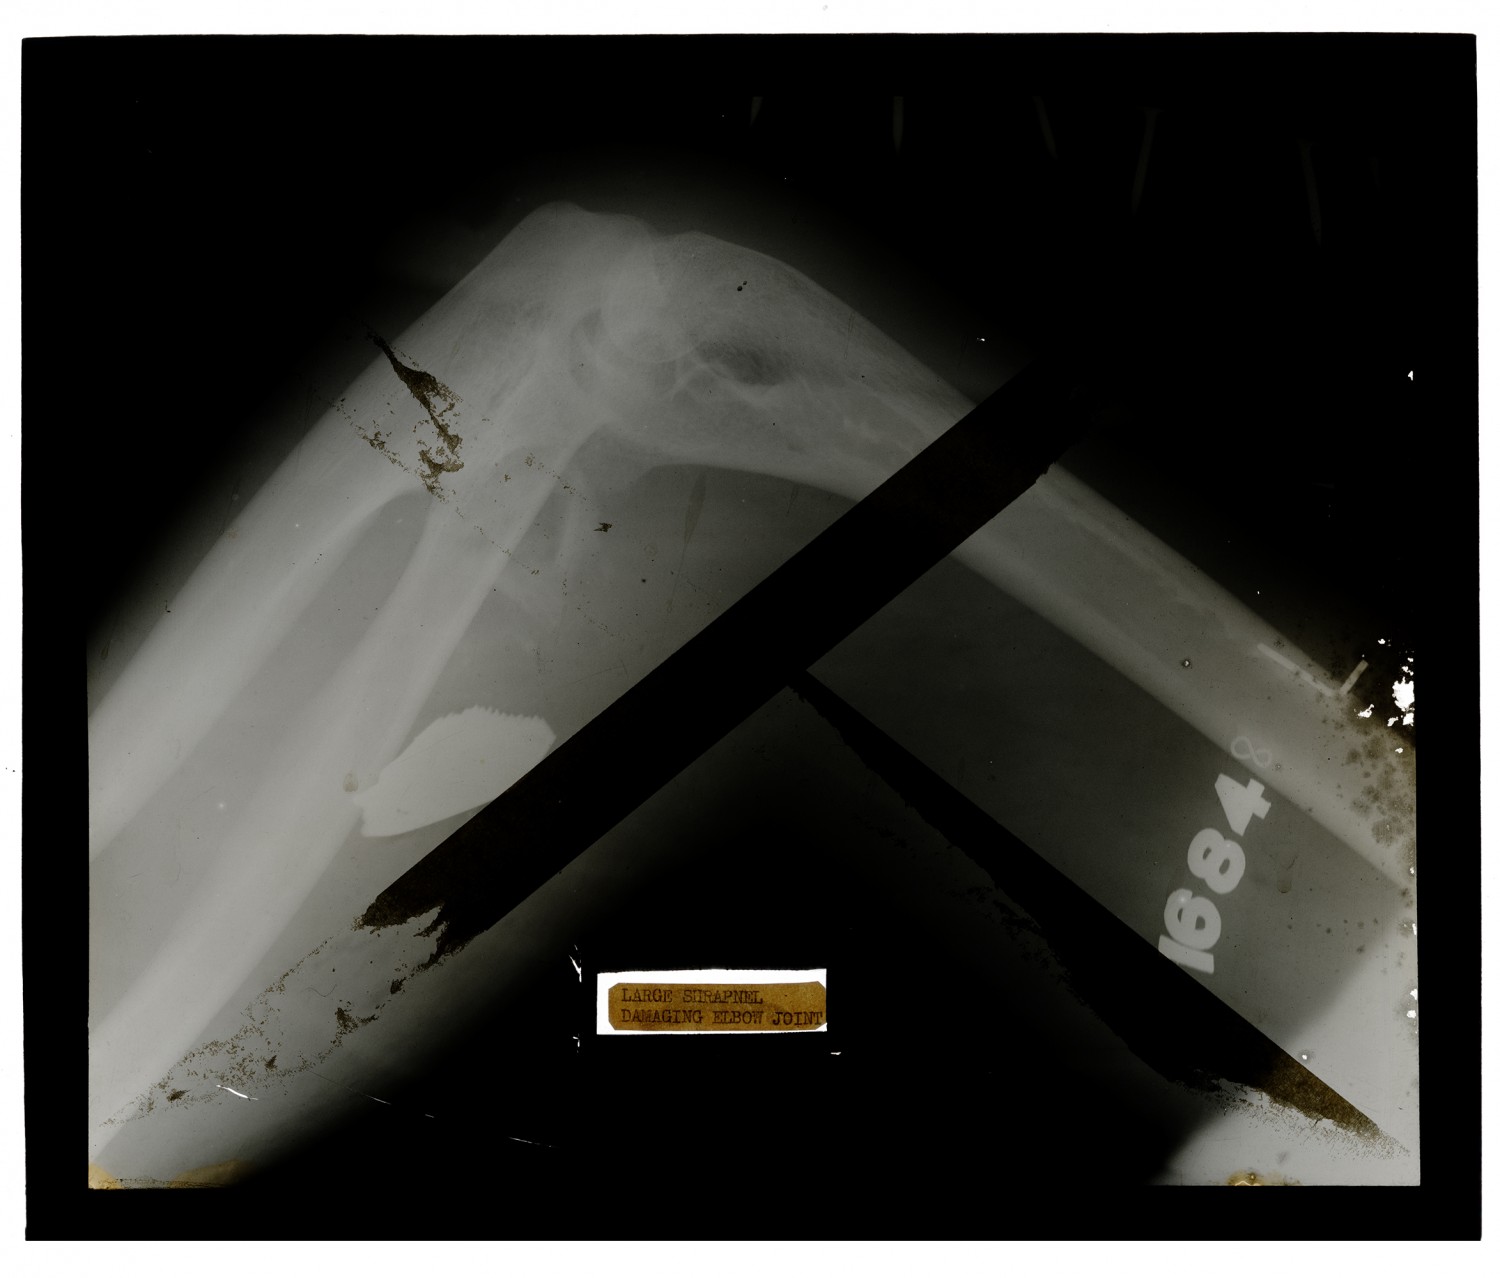

LARGE SHRAPNEL DAMAGING ELBOW JOINT